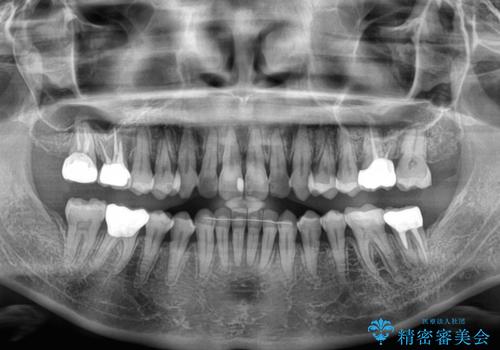

概ね歯列が整ったところで銀歯の全てをセラミッククラウンなどに置き換え、その後インビザラインを1セット使用して仕上げていくこととしました。

矯正治療の後半にはホワイトニングもされ、スッキリした口元に仕上げることができました。